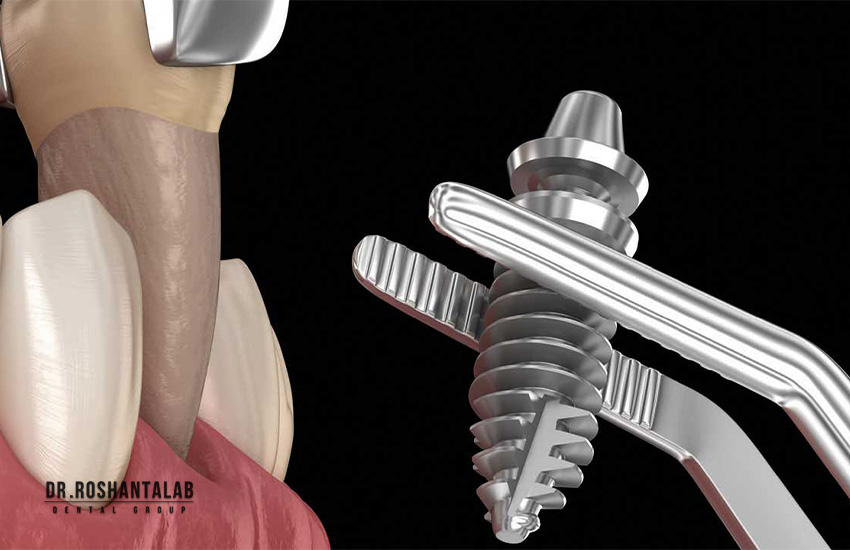

ایمپلنت فوری دندان تکنیکی پیشرفته است که در آن دندان آسیبدیده کشیده شده و همزمان فیکسچر (پیچ تیتانیومی) در استخوان فک کاشته میشود. برخلاف روشهای سنتی، در همان جلسه یک روکش موقت قرار میگیرد تا ظاهر طبیعی حفظ شود. این روش معمولاً ۳ تا ۴ هفته طول میکشد تا روکش دائمی نصب شود. طبق مطالعات، نرخ موفقیت این روش با شرایط مناسب به ۹۵٪ میرسد. آیا این سرعت برای شما جذاب است؟

- کشیدن دندان و کاشت فیکسچر: با بیحسی موضعی، دندان کشیده و ایمپلنت در همان روز نصب میشود.

- نصب روکش موقت: روکش موقت برای حفظ ظاهر و عملکرد قرار میگیرد.

- بهبودی و روکش دائمی: پس از ۳-۴ هفته که استخوان با ایمپلنت جوش میخورد، روکش دائمی نصب میشود.